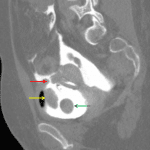

Practice Cases